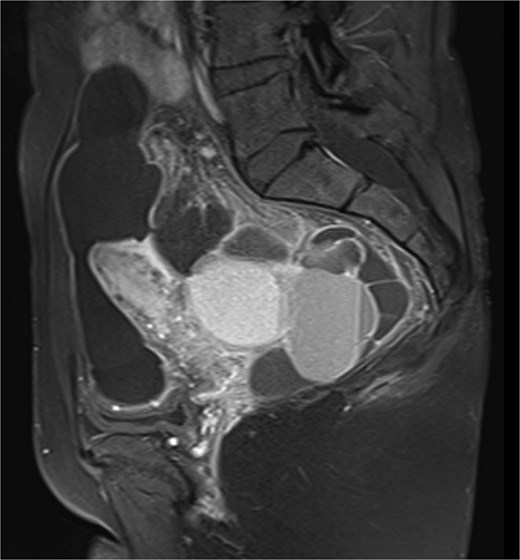

Pelvic ultrasound showed a large multicystic lesion occupying most of the pelvic cavity and pressing on nearby organs. Magnetic resonance imaging (MRI) provided a clearer picture, revealing a multilocular cystic mass displacing the uterus, ovaries, and rectosigmoid colon (Figs 1 and 2). Some cystic areas contained clear fluid, while others showed haemorrhagic or proteinaceous content, raising suspicion of a mucinous cystadenoma or borderline ovarian tumor.

Sagittal T2-weighted pelvic MRI demonstrating a large multilocular cystic lesion occupying the pelvic cavity and displacing adjacent organs.